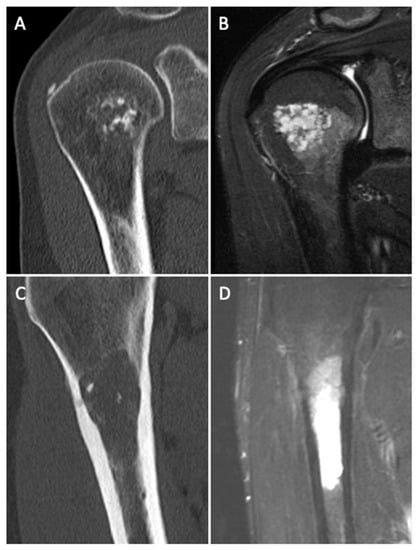

Differentiating Enchondromas and Atypical Cartilaginous Tumors in Long Bones with Computed Tomography and Magnetic Resonance Imaging

3.4. CT and MR Imaging Criteria